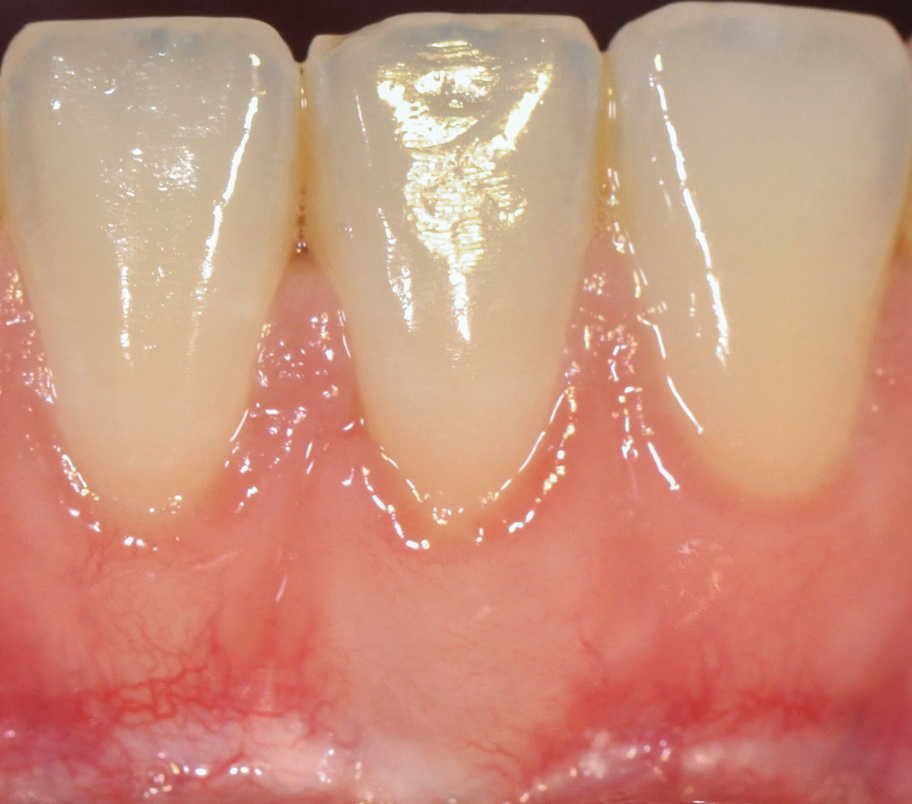

The workshop's group on periodontal soft-tissue root coverage procedures evaluated the predictability of root coverage procedures for single- and multiple-tooth Miller Class I and II10 periodontal recession defects. The workshop concluded that predictable root coverage was possible for Miller Class I and II recession involving a single tooth. When compared with the use of acellular dermal matrix graft (ADMG) (donor tissue) or EMD (porcine origin), procedures using a subepithelial connective tissue graft (SCTG) harvested from the patient's palate provided the best root coverage outcomes in conjunction with a coronally advanced flap.11 As alternatives to autogenous donor tissue, the workshop found strong evidence to support the use of an ADMG or EMD in conjunction with a coronally advanced flap and limited evidence to support the use of platelet-derived growth factor and xenogeneic collagen matrix.11 In addition, root coverage procedures were found to be effective for Miller Class I and II recession defects affecting multiple teeth, although the evidence is limited.11 Figure 1 and Figure 2 show the pretreatment and 1-year postoperative views of a soft-tissue root coverage treatment with SCTG and EMD that used a coronally advanced flap and a tunneling procedure. Figure 3 and Figure 4 depict the pretreatment and 3-year postoperative views of a root coverage procedure with ADMG and EMD that used a coronally advanced flap and a tunneling procedure (this patient was noncompliant following surgery and did not return to the office until the 3-year postoperative appointment).

(2.) Postoperative view after one year following treatment with SCTG (harvested from palate) and EMD using a coronally advanced flap and a tunneling procedure.

Figure 2

(4.) Postoperative view after 3 years following treatment with ADMG and EMD using a coronally advanced flap and a tunneling procedure (the patient was noncompliant following surgery and did not return to the office until the 3-year postoperative appointment).

Figure 4